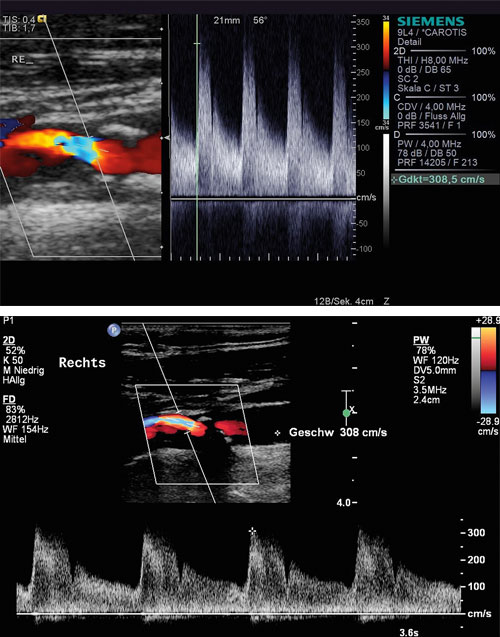

Diese Stenose der A. carotis interna (mit zwei unterschiedlichen Ultraschallsystemen gemessen) blieb über 15 Jahre unverändert bei 70 %. Diese Stenose der A. carotis interna (mit zwei unterschiedlichen Ultraschallsystemen gemessen) blieb über 15 Jahre unverändert bei 70 %. © Arning C. Hamburger Ärzteblatt 2023; 77: 28–30 © Hamburger Ärzteverlag, Hamburg